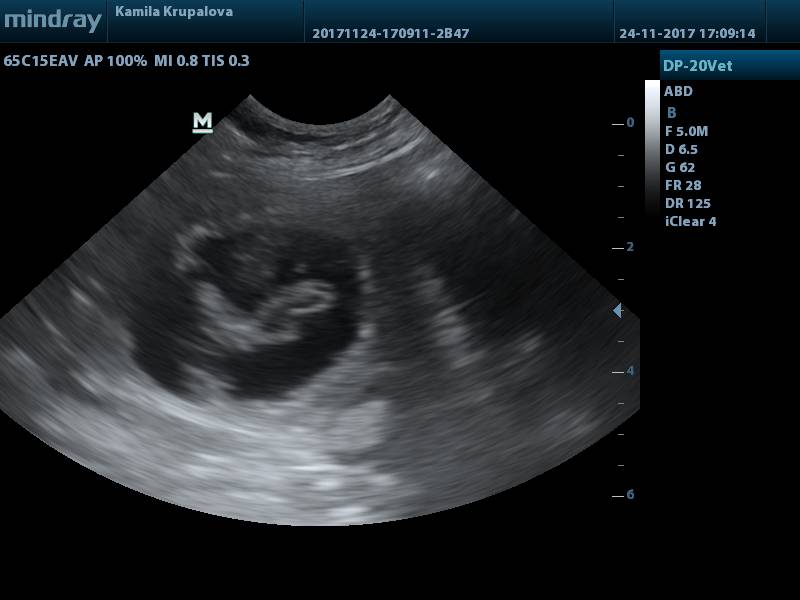

BŘEZOST POTVRZENA